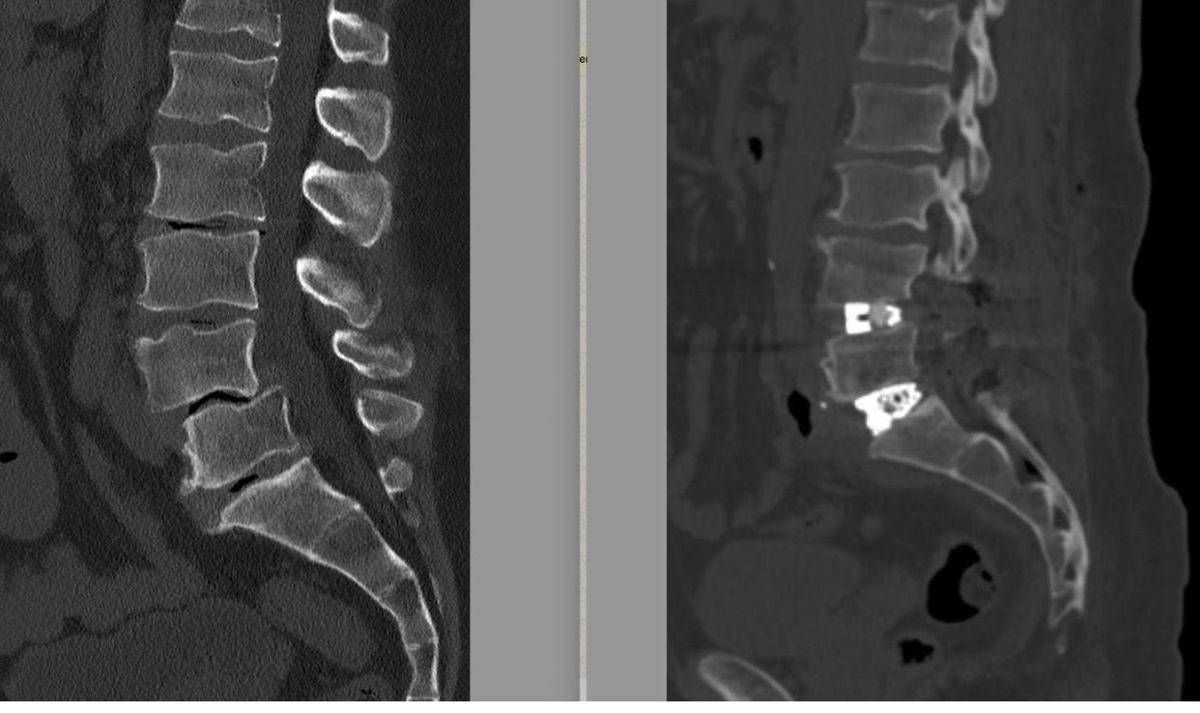

La diagnosi era di spondilolistesi tra la quarta e la quinta vertebra lombare (L4-L5), una patologia degenerativa cronica caratterizzata dallo scivolamento progressivo di una vertebra sull’altra, associata a una discopatia del disco intervertebrale L5-S1. Nel tempo – sottolineano gli esperti – questa deformità determinava una compressione significativa delle radici nervose, provocando una sciatalgia bilaterale invalidante, con dolore irradiato agli arti inferiori che peggiorava in posizione eretta e durante le attività quotidiane e lavorative, compromettendo in modo rilevante la qualità di vita.

Un passaggio fondamentale nella pianificazione dell’intervento chirurgico – illustra la nota – è stato lo studio dei cosiddetti ‘parametri spino-pelvici’, effettuato su una radiografia dell’intera colonna vertebrale. Questi supportano il chirurgo vertebrale nella scelta dell’approccio chirurgico più corretto e della tipologia di impianti da utilizzare in base al grado di lordosi da ripristinare. “Oggi la chirurgia vertebrale non si limita a liberare i nervi o a stabilizzare un segmento ritenuto instabile – precisa il neurochirurgo e chirurgo vertebrale – ma punta a ricostruire un assetto posturale il più possibile fisiologico. Il mancato rispetto e, quando possibile, ripristino di questi parametri può portare nel tempo al fallimento del costrutto impiantato nella colonna vertebrale o alla prematura degenerazione dei segmenti della colonna adiacenti a quello trattato”.

L’intervento è stato eseguito all’inizio di febbraio 2026 ed è durato circa 6 ore, riferiscono i sanitari. A 12 ore dalla chirurgia è stata eseguita una Tac addominale senza mezzo di contrasto per escludere eventuali complicanze legate all’accesso anteriore, mentre una radiografia in posizione eretta ha consentito di verificare immediatamente la qualità della correzione ottenuta. Il decorso post-operatorio è stato regolare. Il paziente si è risvegliato con un miglioramento sostanziale della sintomatologia sciatalgica e con un dolore limitato alle ferite chirurgiche, gestibile con comuni analgesici. In assenza di complicanze neurologiche o generali, è stato dimesso in seconda giornata post-operatoria. Rientrato a casa, il paziente prosegue il monitoraggio clinico con l’équipe di Chirurgia vertebrale di Tiberia Hospital. Nelle prime settimane, la riabilitazione consiste principalmente nella deambulazione e nella ripresa graduale delle attività quotidiane senza caricare la colonna.